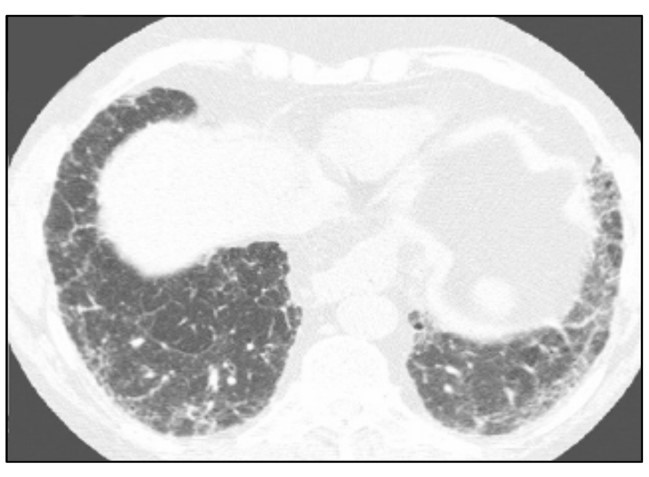

HRCT: UIP PATTERN5,6,18

- Subpleural, basal predominance

- Heterogeneous distribution of areas of normal lung and fibrosis; may also be diffuse and asymmetric

- Honeycombing with or without traction bronchiectasis/bronchiolectasis

Overlay of reticular pattern and mild ground glass opacity (GGO)

Image courtesy of and used with permission from Sudhakar Pipavath, MD.

A UIP pattern on HRCT, paired with a lack of identifiable cause, is sufficient to diagnose IPF.5,6,18